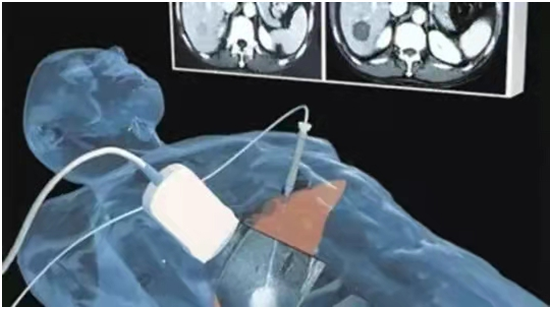

經(jīng)過科室內(nèi)部充分討論,最終為患者擬定了治療方案,在超聲科、介入科的通力合作下,患者在局部麻醉下順利完成了“TACE”+微波消融手術(shù)。

患者在手術(shù)中

全程保持清醒狀態(tài)且無痛感

手術(shù)時間不超過1小時

術(shù)后馬上就可以下床活動了

而消融治療則是指在超聲影像的引導(dǎo)下,將消融針從皮膚穿刺入肝臟腫瘤,消融針連接能量源,通過高溫、冷凍、高壓電等不同的消融方式,直接將消融針周邊的腫瘤組織滅活。